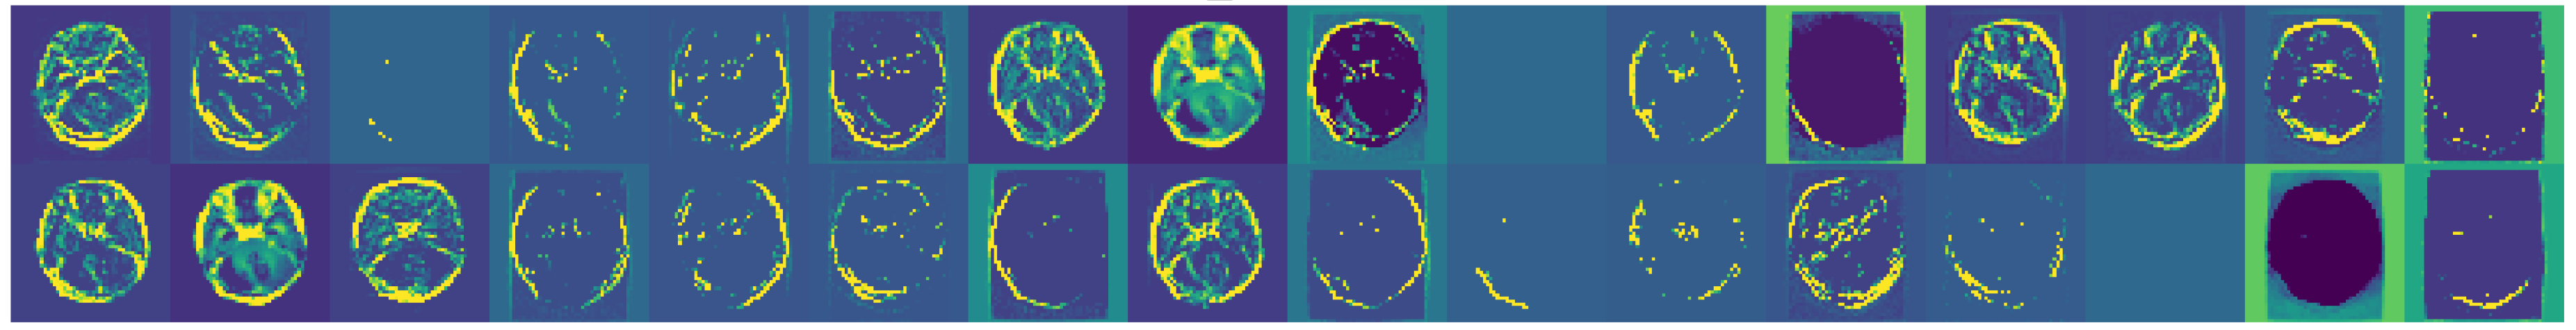

3.1. Dataset Overview

- Glioma: Cancerous tumors in glial cells.

- Meningioma: Non-cancerous tumors originating from the meninges.

- No Tumor: Normal brain scans without detectable tumors.

- Pituitary: Tumors affecting the pituitary gland, which can be either cancerous or non-cancerous.

3.2. Data Preprocessing

4.4. Data Augmentation